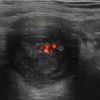

Mucocele ruột thừa

» Thông tin: Nam giới – 71 tuổi.

» Lâm sàng: Đau hố chậu phải mạn tính.